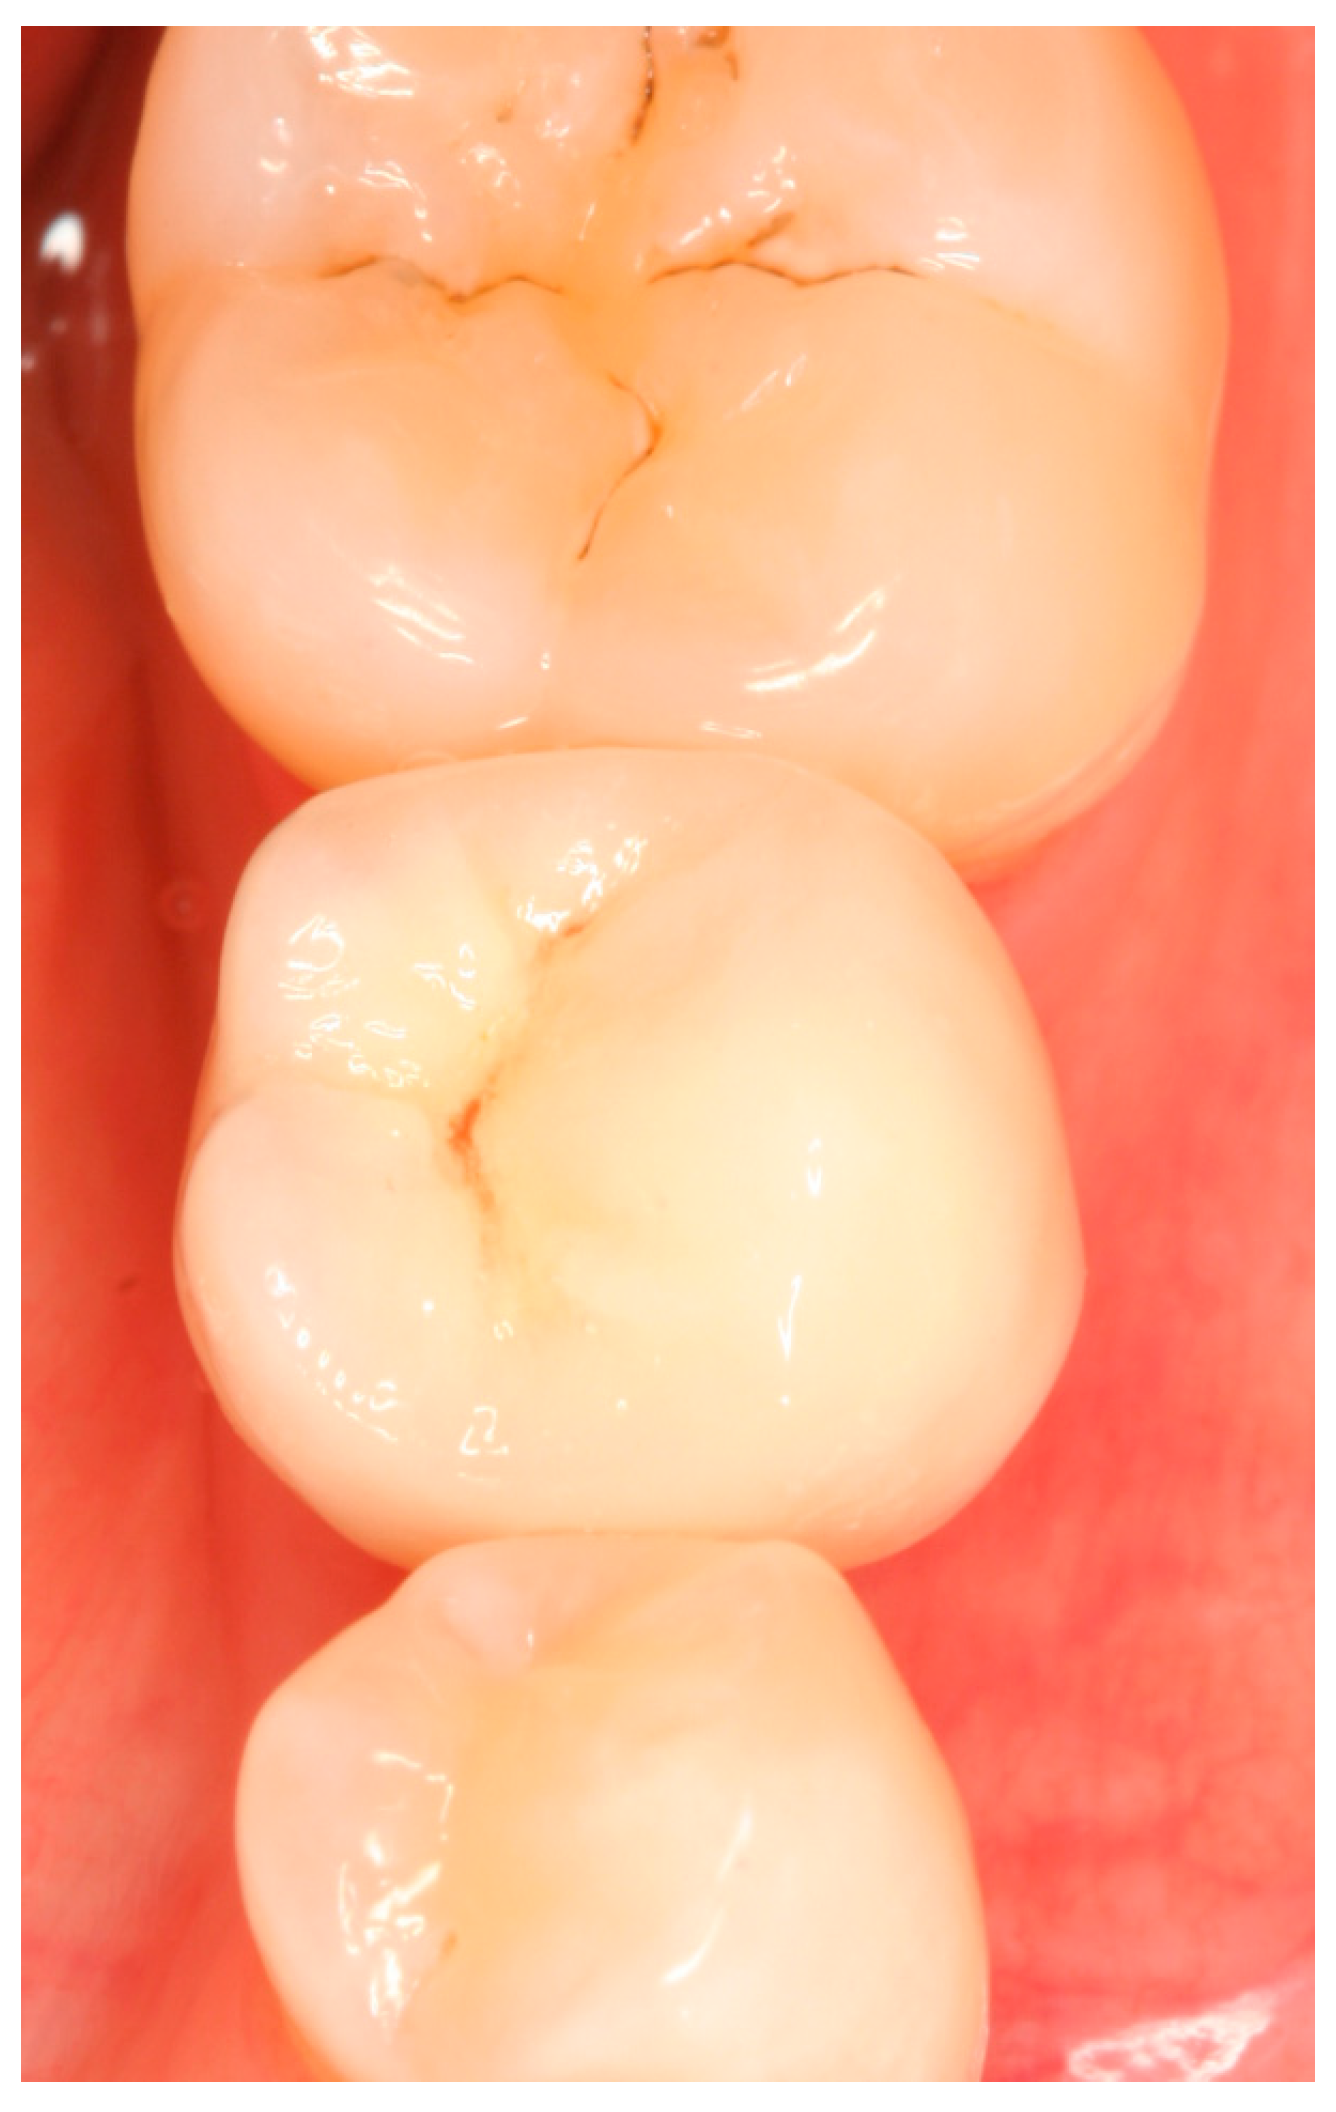

Clinical situation at the 3-year follow-up. Occlusal view.

Clinical situation at the 5-year follow-up. Occlusal view.

Situation after crown cementation. Occlusal view.

Clinical situation at the 1-year follow-up. Occlusal view.

Clinical situation at the 3-year.